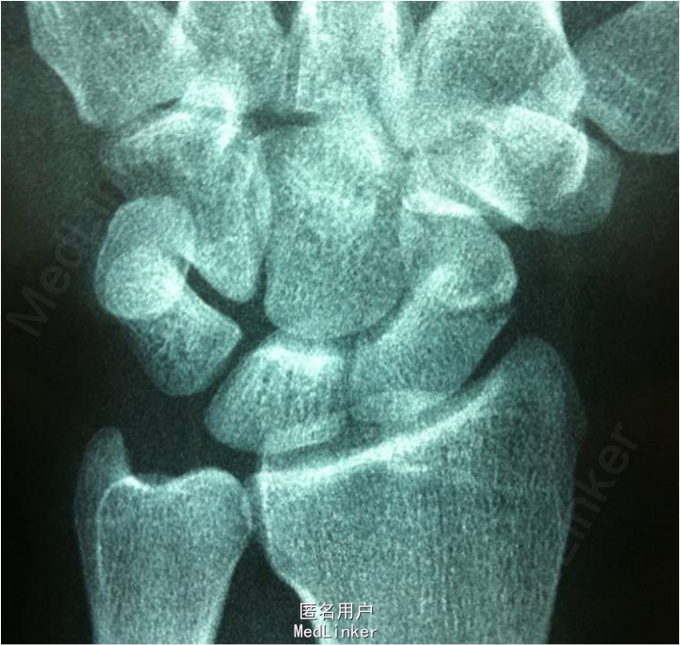

患者男,30岁,因”摔伤致右腕关节疼痛2周余”入院。患者2周前因摔伤后出现右腕关节疼痛,伴活动障碍。现患者为求进一步诊治前来我院就诊,余未见明显异常。

查体:右腕关节稍肿胀,腕关节桡侧间隙压痛,石膏固定良好,无皮损,无骨摩擦音。肢端血运、感觉、运动可,肌力5级。 X线检查提示:右腕舟状骨骨折

诊断:右腕舟状骨骨折。拟行右腕关节镜检,关节镜监视下行腕舟骨骨折复位内固定(备开放)术。